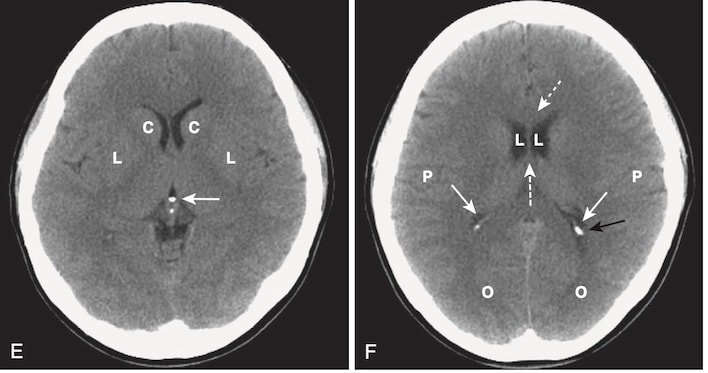

- Một trong hai cơ chế này có thể tạo ra dập não (contusion). Các đụng dập xuất huyết là những xuất huyết, kèm theo phù nề, thường thấy ở phần dưới thùy trán và phần trước thùy thái dương trên hoặc gần bề mặt của não (Hình 10).

- Nhận biết xuất huyết trong não do chấn thương trên CT:

- Đụng dập xuất huyết não có thể xuất hiện dưới dạng nhiều vùng nhỏ, được phân cách rõ ràng với đậm độ cao trong nhu mô não (xem Hình 10, A).

- Chúng có thể được bao quanh bởi một vành giảm tín hiệu (hypodense) do phù nề (xem Hình 10, B).

- Hiệu ứng choán chỗ thường gặp. Hiệu ứng choán chỗ có thể ép các não thất và đẩy lệch não thất thứ 3 và vách ngăn sang bên đối diện. Sự dịch chuyển như vậy có thể gây ra tổn thương não hoặc mạch máu nghiêm trọng.

- Những di lệch này được gọi là thoát vị (herniation). Những bệnh nhân có hiệu ứng choán chỗ đủ lớn có nguy cơ bị thoát vị não qua lều hoặc dưới liềm và tử vong (xem Hình 10, B). Các dạng thoát vị não được mô tả trong Bảng 5.